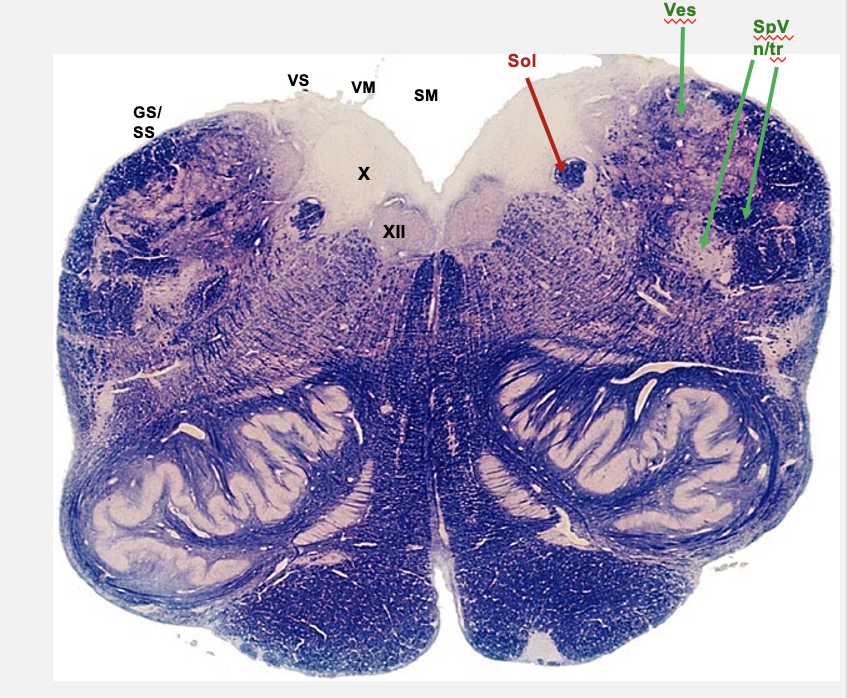

nucleus and tract solitarius

primary visceral sensory nucleus of the brainstem

cranial nerves 7,9,10

rostral portion of nucelus/tract solitarius

receives taste information from cranial nerves 7 (anterior), 9 (posterior) and 10 (epiglottis)

caudal portion of nucleus/tract solitarius

receives visceral information from GI tract (cranial nerve 10)

vestibular nuclei

cochlear nuceli

associated with cranial nerve 8; special sensory nuceli of brainstem

rostral medulla

hypoglossal nucleus

dorsal visceral motor vagal nucelus

nucleus solitarius

vestibular nucelus

nucleus and tract of V

rostral medulla cross section cranial nerve nuclei

cochlear nucleus

pontomeduallary junction cross section cranial nerve nucelus